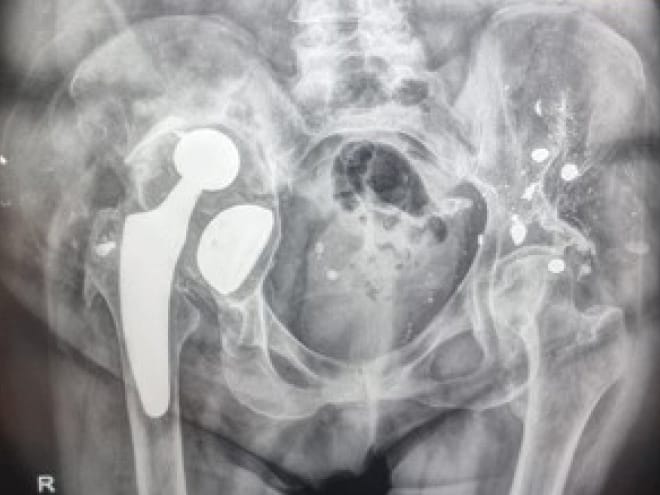

The clinical articles address complementary dimensions of arthroplasty science. Implant safety and fixation are explored through studies on the evolution of metal ions following knee prosthesis implantation and line-to-line cementation in hip arthroplasty, with attention to the "French Paradox". Reconstructive complexity is examined in severe post-traumatic and post-arthroplasty acetabular defects, extending beyond existing classifications. Patellofemoral surgery is contextualized through The Lyon contribution to patellofemoral surgery, tracing the legacy from Albert Trillat to Henri Dejour. The issue is further complemented by a dedicated analysis of ligament balancing and alignment.